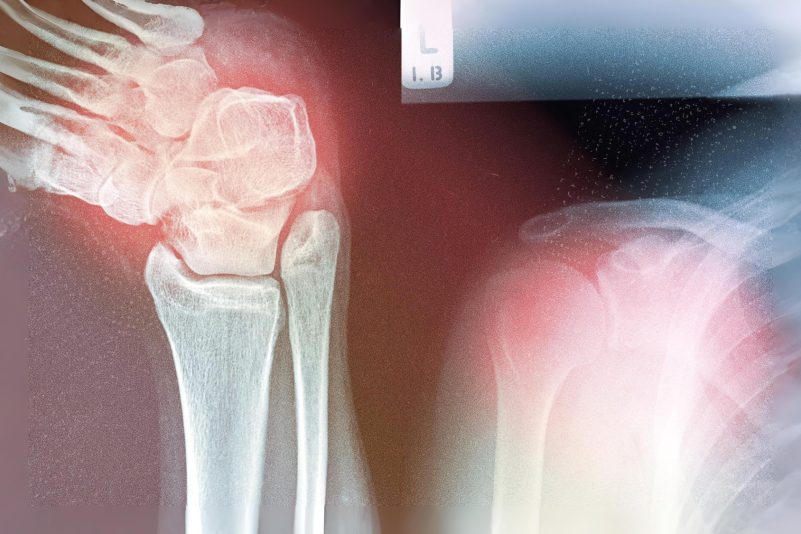

Les troubles musculo-squelettiques chroniques sont désormais la principale cause d’invalidité dans le monde. Ces affections n’affectent pas seulement la mobilité – elles réduisent également la qualité de vie, augmentent le risque de chutes, de fractures et d’hospitalisation.

En 2021, environ 607 millions de personnes vivaient avec l’arthrose – une augmentation de 137 % depuis 1990. La polyarthrite rhumatoïde et la goutte ont également fortement augmenté, respectivement de 125 % et 150 %. Le coût de ces affections est substantiel. Qu’est-ce qui motive l’augmentation rapide des troubles musculo-squelettiques ?